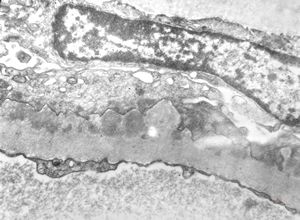

M,17y. | Alport syndrome - split and laminated basement membranes